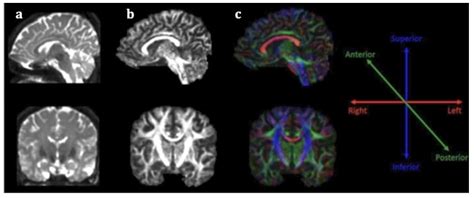

Diagnostic procedures involving the costal structures often include imaging techniques such as X-rays, CT scans, and MRI. These imaging modalities help healthcare professionals visualize the ribs and costal cartilage to identify any fractures, dislocations, or other abnormalities. In some cases, a physical examination may also be sufficient to diagnose conditions related to the costal structures.